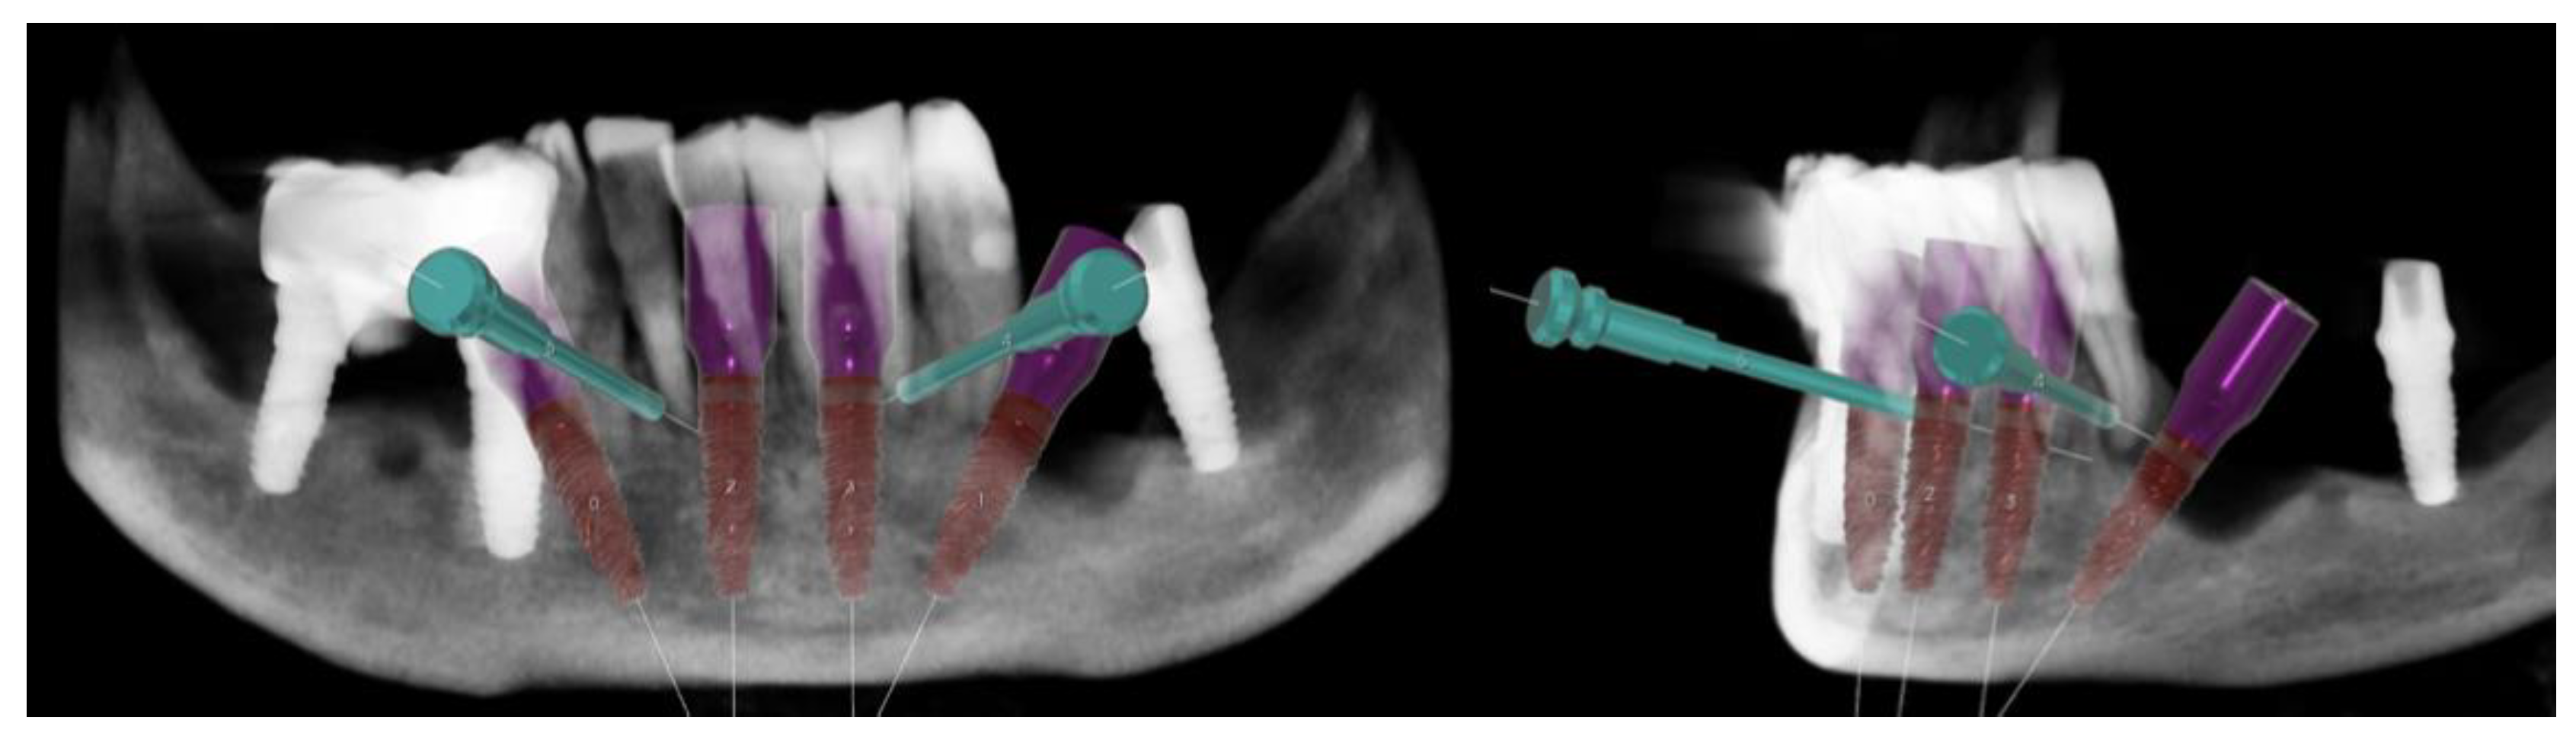

2.1. Planning

Surgical Guide